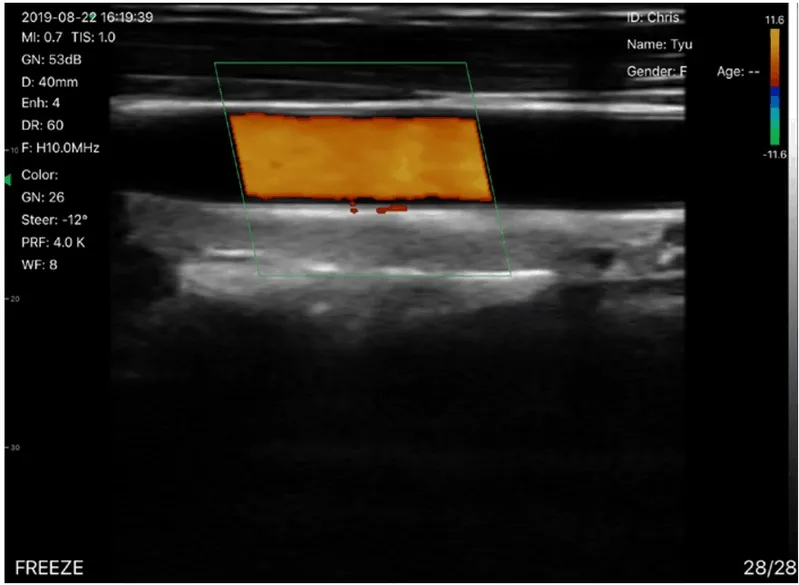

| Sonda lineal de frecuencia: La profundidad de anáLisis de la sonda lineal: Cabezal de sonda lineal radio/ancho: | 7.5MHz/10MHz 20/40/60/100mm 40mm |

Imagen de la sonda de ultrasonidos phased array.